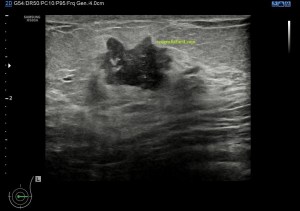

En este caso la paciente llega a la sala con una petición de su urólogo para descartar un problema renal. Al llegar al riñón izquierdo y hacer un recorrido, percibo que el bazo tiene un aspecto muy heterogéneo, y al finalizar el estudio encomendado, volví al bazo y encontré una ecoestructura alterada ecográficamente, heterogénea con gran cantidad de imágenes hiperecogénicas que llenaban todo el órgano.

Observas, semiólogicamente hablando, un bazo con una gran cantidad de lesiones ocupantes de espacio, hiperecogénicas que afectan a toda la ecoestructura. Doppler normal.

Este caso que te presento ya había debutado en otras localizaciones, no afectaba únicamente al bazo, una vez revisada la historia clínica de la paciente, el radiólogo me comentó que la afección era ya conocida, aunque el hecho de verlo en el bazo, era un hallazgo no filiado hasta este momento.

Compara normalidad y patología. Cuando vi este bazo me asusté, pensé que era otra cosa y avisé al radiólogo inmediatamente, saltaron mis alarmas, pero finalmente se comprobó que la sarcoidosis ya era conocida y que mi miedo era infundado. Siempre que veamos anormalidad, debemos tener en cuenta las líneas rojas, lesiones nodulares sólida ocupantes de espacio en órganos compactos del abdomen, pueden ser una de estas líneas rojas y estas deben ser comentadas siempre con el radiólogo responsable.